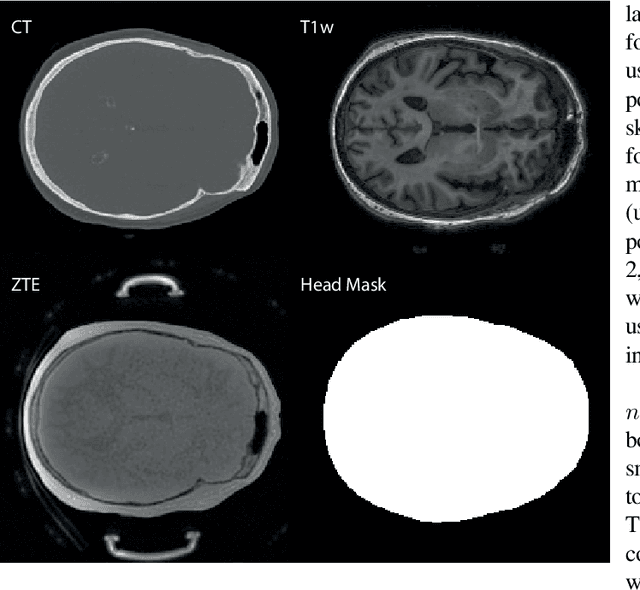

Abstract:Model-based treatment planning for transcranial ultrasound therapy typically involves mapping the acoustic properties of the skull from an x-ray computed tomography (CT) image of the head. Here, three methods for generating pseudo-CT images from magnetic resonance (MR) images were compared as an alternative to CT. A convolutional neural network (U-Net) was trained on paired MR-CT images to generate pseudo-CT images from either T1-weighted or zero-echo time (ZTE) MR images (denoted tCT and zCT, respectively). A direct mapping from ZTE to pseudo-CT was also implemented (denoted cCT). When comparing the pseudo-CT and ground truth CT images for the test set, the mean absolute error was 133, 83, and 145 Hounsfield units (HU) across the whole head, and 398, 222, and 336 HU within the skull for the tCT, zCT, and cCT images, respectively. Ultrasound simulations were also performed using the generated pseudo-CT images and compared to simulations based on CT. An annular array transducer was used targeting the visual or motor cortex. The mean differences in the simulated focal pressure, focal position, and focal volume were 9.9%, 1.5 mm, and 15.1% for simulations based on the tCT images, 5.7%, 0.6 mm, and 5.7% for the zCT, and 6.7%, 0.9 mm, and 12.1% for the cCT. The improved results for images mapped from ZTE highlight the advantage of using imaging sequences which improve contrast of the skull bone. Overall, these results demonstrate that acoustic simulations based on MR images can give comparable accuracy to those based on CT.